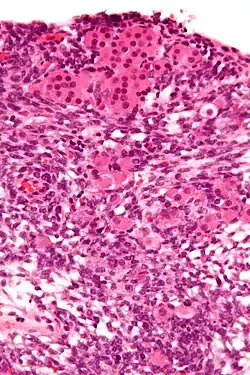

-

High magnification micrograph of a Leydig cell tumour. H&E stain. -